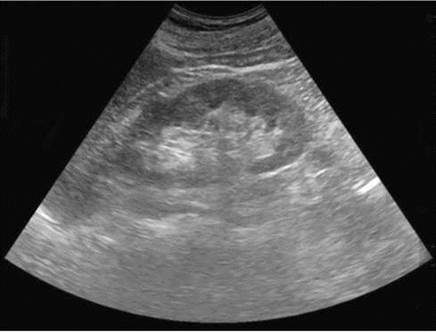

Рис. 4.12. Сонограмма. Гидронефроз: 1 - выраженное расширение лоханки и чашечек со сглаживанием их контуров; 2 - резкое истончение паренхимы почки

Характер очаговой патологии почки определяется сонографической картиной выявленных изменений - от анэхогенного образования с дорсальным усилением до гиперэхогеннего образования, дающего акустическую тень. Анэхогенное жидкостное образование в проекции почки по своему происхождению может быть кистой (рис. 4.11) или расширением чашечек и лоханки – гидронефрозом (рис. 4.12).